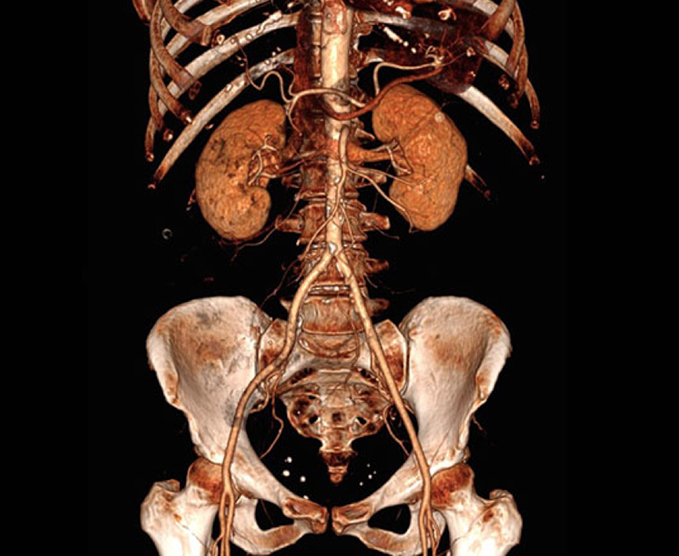

Angiotomografías

La angiografía por TC (ATC) combina una tomografía computarizada con la inyección de una tintura de contraste. TC significa tomografía computarizada. Esta técnica es capaz de crear imágenes de los vasos sanguíneos para detección de anomalías.

- Aorta toráccica y abdominal

- Angiografía de MPS